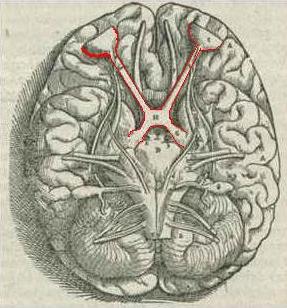

[[File:1543,Visalius'OpticChiasma.jpg|thumb|optic Chiasm]] | |||

The [[Optic Chiasm]] is located at the bottom of the brain immediately below the [[Hypothalamus]]. One of the most important functions of the [[Hypothalamus]] is to link the nervous system to the endocrine system via the [[Pituitary Gland]]. The [[Optic Chiasm]] allows the images from either side of the field from both eyes to be transmitted to the appropriate side of the brain, combining the sides together. This allows for parts of both eyes that attend to the right visual field to be processed in the left visual system in the brain, and vice versa. This is linked to skin sensation.<ref>[http://en.wikipedia.org/wiki/Optic_chiasm Optic Chiasm]</ref> | |||

The Optic Chiasm is located at the bottom of the brain immediately below the Hypothalamus. One of the most important functions of the Hypothalamus is to link the nervous system to the endocrine system via the Pituitary Gland. The Optic Chiasm allows the images from either side of the field from both eyes to be transmitted to the appropriate side of the brain, combining the sides together. This allows for parts of both eyes that attend to the right visual field to be processed in the left visual system in the brain, and vice versa. This is linked to skin sensation.[2]